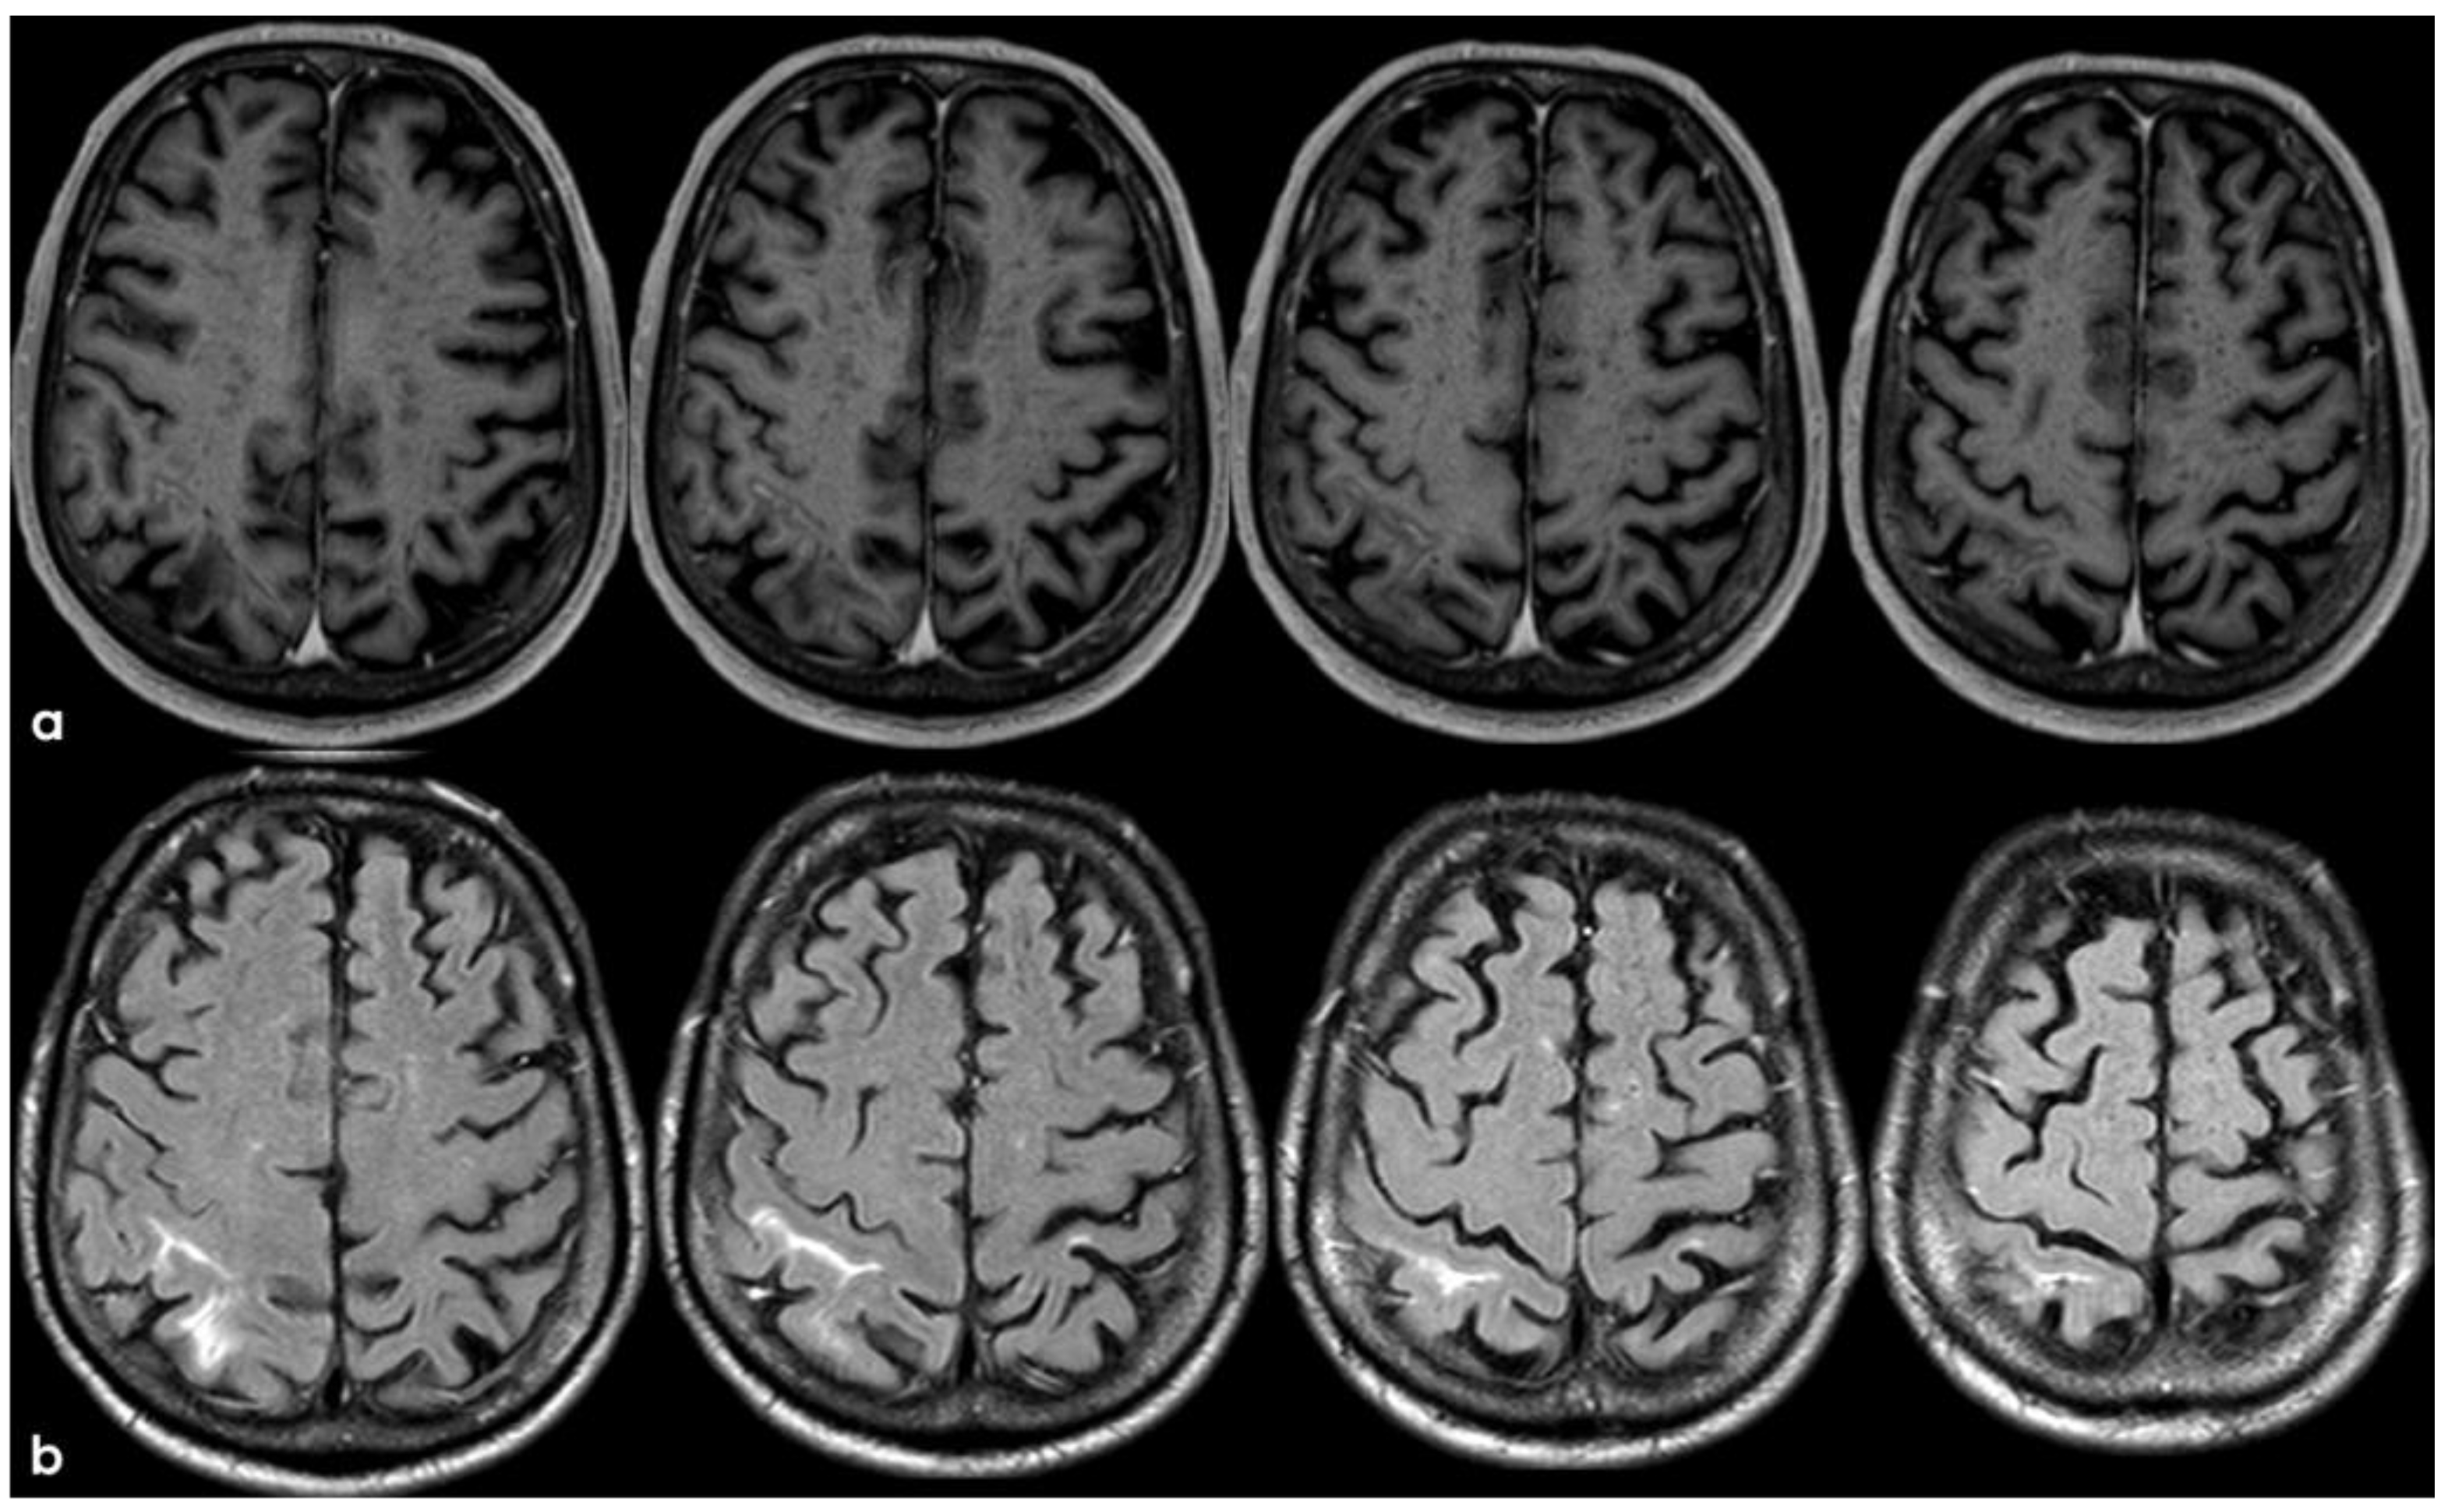

2. December 2013: Sulcal SAH and TFNEs

3. May 2014: CAA-Related Inflammation